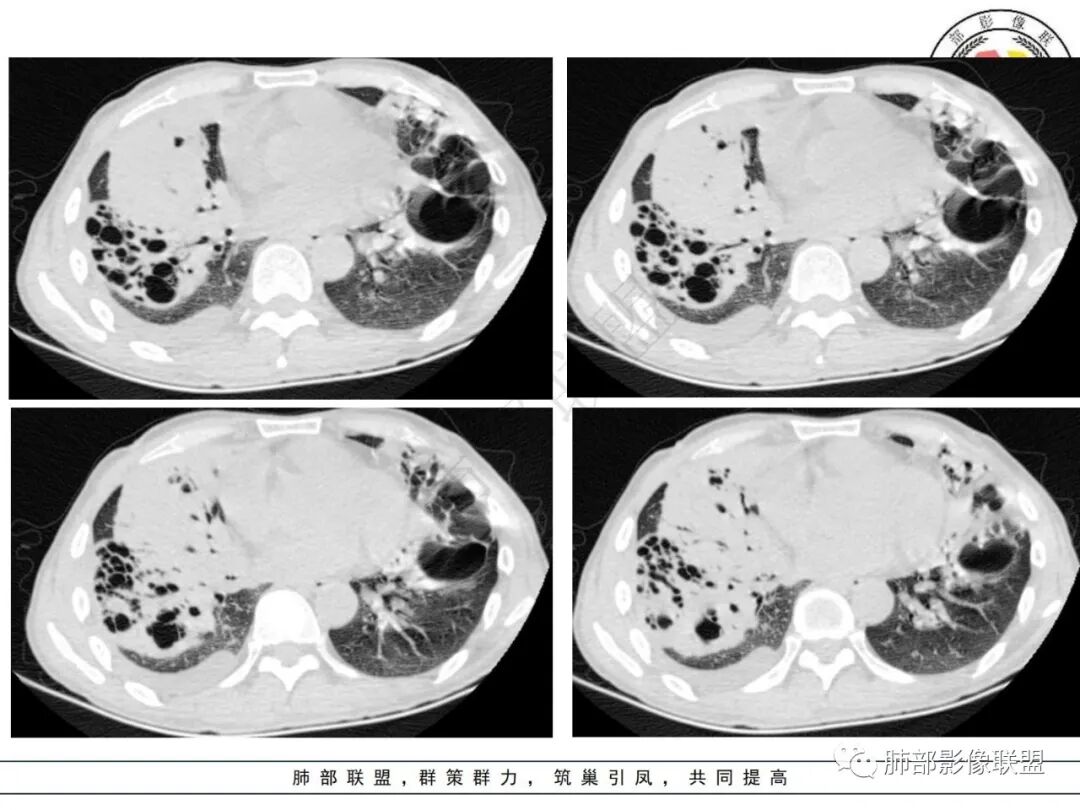

衡妈:有没有可能吸入了啥引起的感染,比如汽油。两肺门周围较大实变及囊腔型病灶,右侧实变可见扩张的支气管,夹杂磨玻璃影;左侧囊壁略厚,囊腔不规则,内多分隔,近端支气管感觉有堵塞。其余两肺散在小空洞性病灶。纵隔可见明显肿大淋巴结。先考虑感染性病变,鉴别肿瘤性病变,淋巴瘤。

张延军:右肺大片实变,边缘膨隆,上叶前段支气管阻塞,实变区内支气管扩张,左肺大的厚壁囊腔,近端见支气管进入(感觉支气管活瓣作用),右侧胸腔积液,中年男性,气促一月。恶性放前面,淋巴瘤?腺癌?(左右侧),鉴别,根据实验室检查和临床症状除外诺卡菌感染。

丽:双肺多发结节及片状实变密度影,实变内可见支气管穿行,走形僵直,部分见多发囊腔,内可见分隔,壁厚薄不均,支气管管壁略增厚,右侧胸腔积液,考虑恶性,淋巴瘤,鉴别囊腔型腺癌。

小兜:男,53岁,气促入院。CT示双肺多发实变影,右肺为著,左肺可见较大分隔囊腔,壁不均匀增厚,右肺可见多发支气管扩张伴周围实变影,右肺较大实变可见支气管截断,内可见支气管充气征,纵隔多发肿大淋巴结,综上所述考虑恶性,淋巴瘤可能。

宇宙:右肺肿块,边缘膨隆,其内支气管扩张、扭曲,少许坏死,上叶前段支气管阻塞,左肺囊腔,壁薄厚不均,其内见分隔,两肺另见多发结节,纵膈淋巴结肿大,右侧胸水,考虑腺癌,鉴别淋巴瘤。

放射线:双肺可见多发斑片状密度增高影,部分可见空泡影,右肺大片实变病灶内见支气管扩张影及斑片状低密度坏死区,边界不清,部分支气管开口阻塞,与胸壁之间少量积液,左肺上叶囊腔型病变,内部可见分隔,该患者亚急性病程,白细胞不高,无发热,考虑二元论右肺腺癌?淋巴瘤?左肺囊性腺瘤样畸形,鉴别结核,马尼。

良孑:中年男性,亚急性起病,双肺多发多形病变,可见树芽征,左病灶呈多囊改变,囊内分格呈车辐征,右肺巨大胖块,支气管截断闭塞,纵隔内可见肿大淋巴结,支持多元论,考虑奴卡,TB(左肺车辐征支持TB)右肺巨大肿块考虑恶性占位腺癌可能。

1.病例特点:中年男性,气促,中长病程。贫血明显,无发热。实验室轻度异常(C反应蛋白升高)。双肺多发结节、片状影,边界可分辨,多见支气管穿行,走形僵直。左肺上叶较大囊腔,腔内分隔明显,壁薄不均,可见结节样增厚,相邻肺组织膨胀不全。右肺上叶块影巨大,多支气管穿行,前段支气管闭塞,后段支气管扩张。余支气管管壁前段增厚。右上纵隔多发肿大淋巴结。右侧胸腔积液。